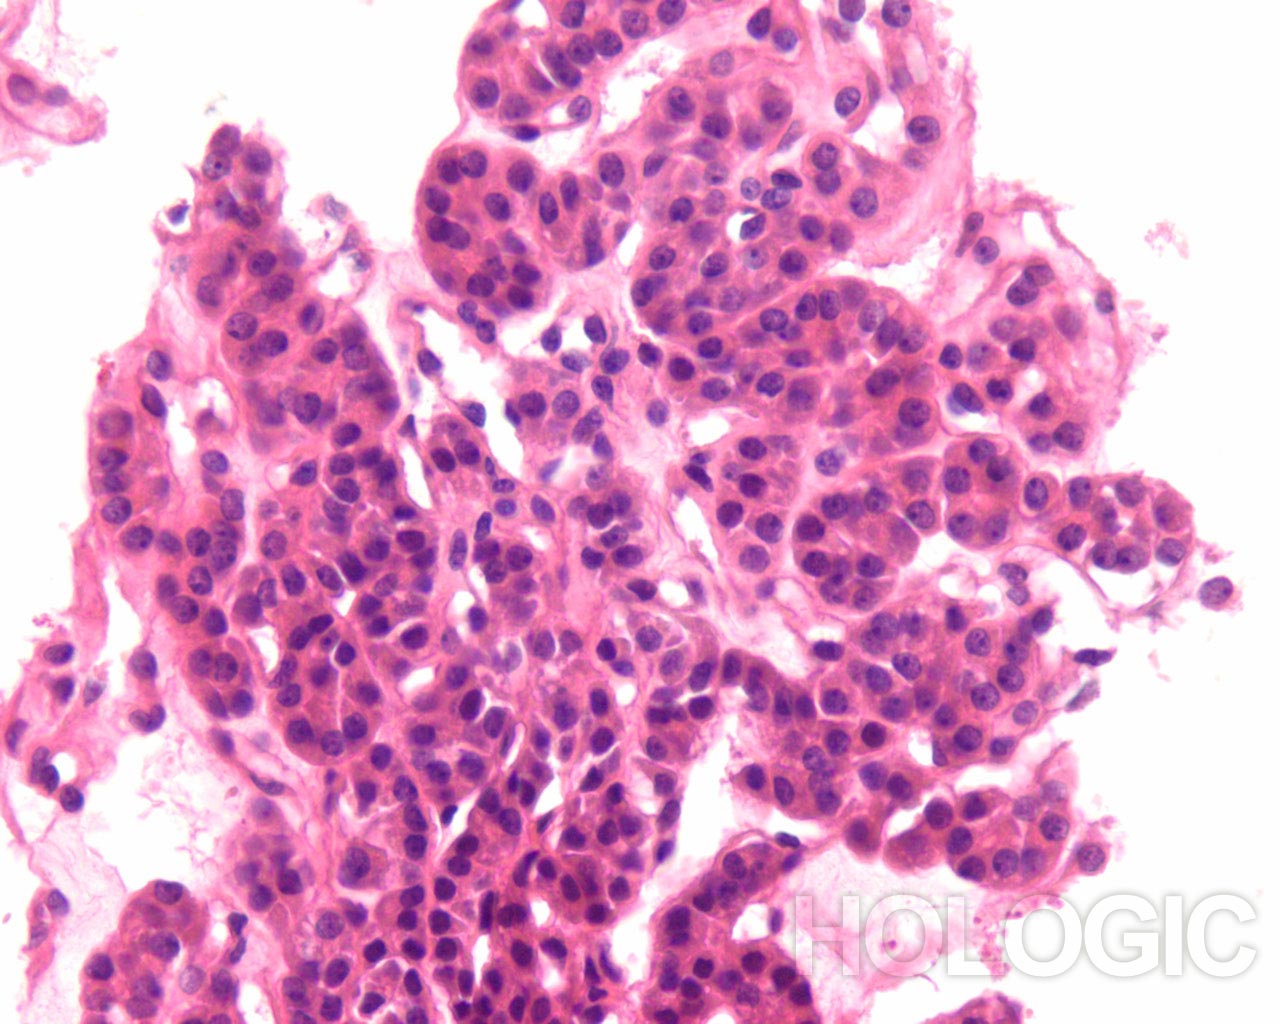

Papillair schildkliercarcinoom is een gemakkelijke diagnose als de nucleaire kenmerken goed ontwikkeld zijn en het monster goed is gepreserveerd. De beste diagnostische kenmerken van papillair schildkliercarcinoom zijn fijn verdeeld chromatine en een onregelmatige nucleaire envelop[2]. Het is interessant dat papillair schildkliercarcinoom het eerste voorbeeld is van een kanker waarbij de diagnostische nucleaire kenmerken rechtstreeks gerelateerd zijn aan de genen die de kanker veroorzaken (besproken in [10]). Een reeks van verschillende onregelmatigheden van de nucleaire envelop kan aanwezig zijn [11]. De chromatine van een papillair schildkliercarcinoom is verdeeld in erg fijne deeltjes en aangezien een groot deel van de chromatine gelijkmatig aan de nucleaire envelop kleeft, heeft zelfs een kleine vouw als gevolg dat de chromatine in de nucleaire envelop er uitziet als een lineair aggregaat of een langwerpige groef. Vooral intranucleaire cytoplasmische inclusies zijn kenmerkend voor een papillair schildkliercarcinoom, maar deze kunnen ook worden aangetroffen bij medullaire schildkliercarcinoom. Deze intranucleaire cytoplasmische inclusie ziet eruit als een scherpe demarcatie die afkomstig is van het heterochromatine in de nucleaire envelop, waardoor het een duidelijke donkerpaarse begrenzing van het cytoplasma vormt. Intranucleaire cytoplasmische inclusies komen zelden voor bij folliculaire neoplasmen [2].

Folliculaire neoplasmen tonen in tegenstelling tot een papillair schildkliercarcinoom compacte aggregaten van heterochromatine. Het is onze ervaring dat de kern van een papillair carcinoom grofweg kan worden onderscheiden van kernen van folliculaire carcinomen, doordat papillaire schildkliercarcinomen vaak meer lineaire aggregaten chromatine vertonen (erg oppervlakkige vouwen van de nucleaire envelop) dan ronde of geklonterde chromatinemassa’s. Deze kenmerken worden hieronder geïllustreerd.